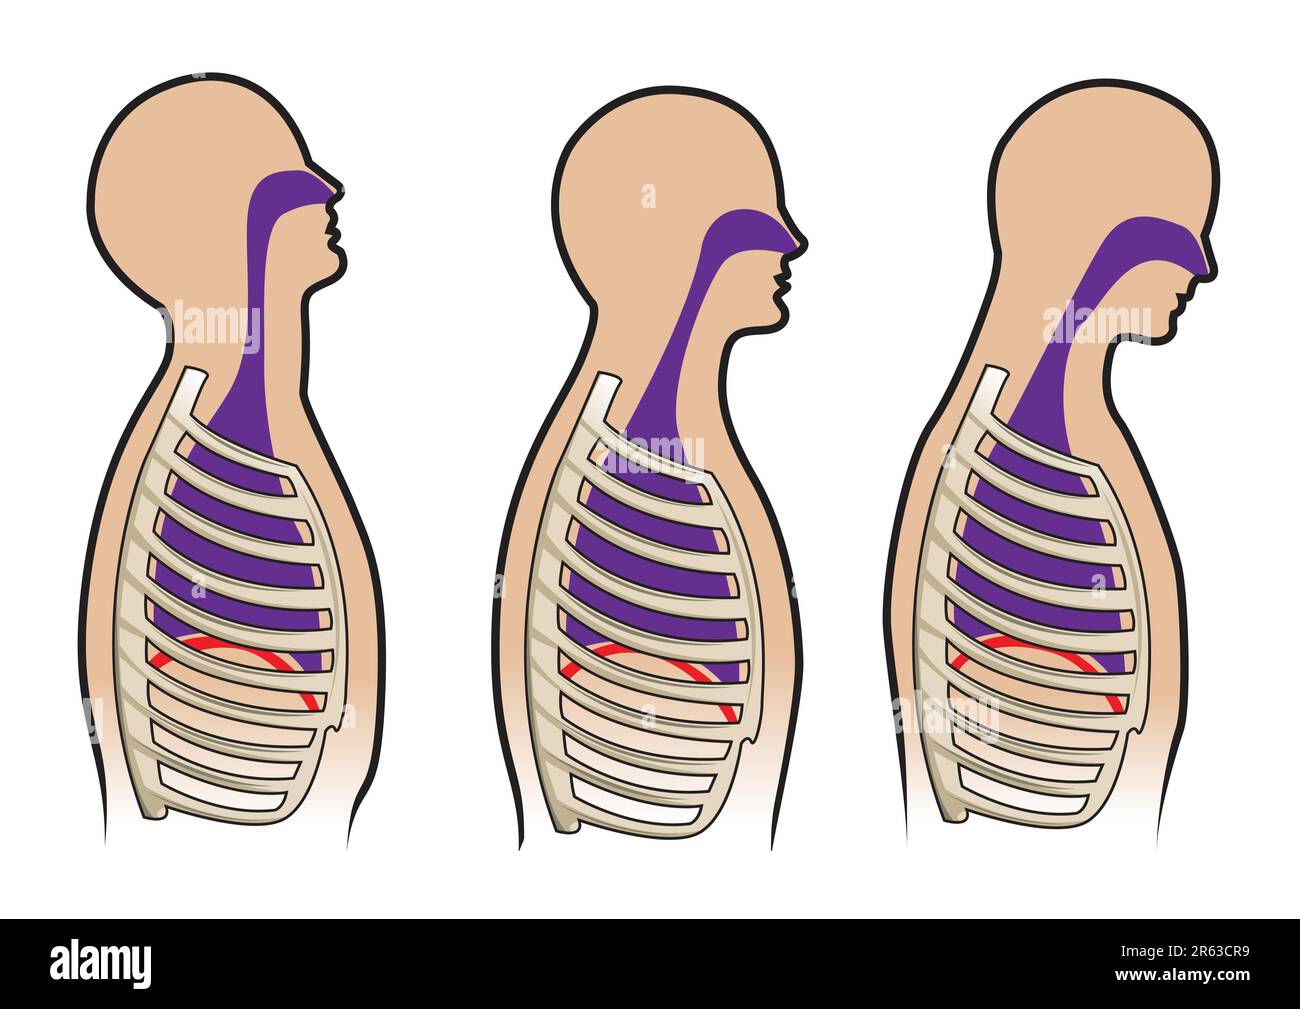

Human respitory system and breathing diagram in vector Stock Vectorhttps://www.alamy.com/image-license-details/?v=1https://www.alamy.com/human-respitory-system-and-breathing-diagram-in-vector-image554495629.html

Human respitory system and breathing diagram in vector Stock Vectorhttps://www.alamy.com/image-license-details/?v=1https://www.alamy.com/human-respitory-system-and-breathing-diagram-in-vector-image554495629.htmlRF2R63CR9–Human respitory system and breathing diagram in vector